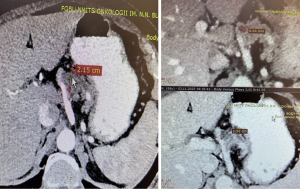

Patient 4, a 75-year-old female, without any clinical manifestations but with a history of chronic pancreatitis and diabetes mellitus. CT and EUS examinations revealed multiple IPMNs resulting in extensive cystic transformation of the pancreatic tissue (Figure 5).

However, it remained unclear which cysts were linked to the main pancreatic duct, complicating the choice of lesions for FNB. Consequently, DAB was performed as an alternative. While no pathological cells were identified, the CEA level exceeded 1,000 ng/mL. Given the connection of the cysts with the main pancreatic duct and the elevated CEA level, a decision was made to proceed with total pancreatectomy. Subsequent histological examination confirmed multifocal IPMNs with a high degree of dysplasia, pTis. After 8 months of follow-up, a CT scan showed no signs of progression.